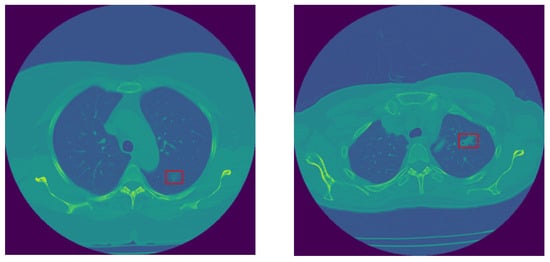

In this study, we use the in-house dataset initially introduced in [30], and include five additional cases obtained from the same institution. This dataset contains volumetric chest CTs (1–3 mm slice thickness) of 114 SSNs, which were biopsy-proven adenocarcinoma spectrum disease lesions. The number of slices varies among patients; however, the collective count totals 925 across all cases. SSNs were categorized into two groups according to their pathological findings and the similarity in their survival rates, as follows: The low-risk group 1 (G1) included 28 pre-invasive lesions (AAH and AIS) and 30 minimally invasive nodules, totaling 58 low-risk lesions, and the high-risk group 2 (G2) included 56 invasive adenocarcinomas. All nodules were surgically resected. CT scans were acquired without contrast medium administration in one of the 2 scanners of a single institution (Aquilion One 64 and 320 detector row CT, Canon Medical Systems, Otawara, Japan). The technical parameters used were 100 to 135 kVp, 80 to 120 mAs, 1–3 mm slice reconstruction, gantry rotation time 0.35 s, and FOV 35–40 cm [30]. The last CT obtained before the resection date was chosen for the purpose of this research study. Examples of invasive and non-invasive nodules are shown in Figure 2.

Figure 2. Sample non-invasive (left) and invasive (right) lung nodules.